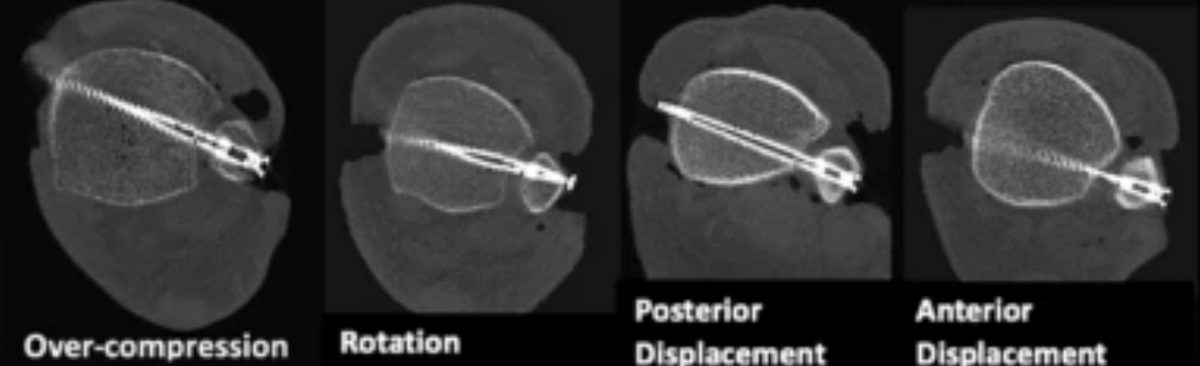

Репозиция синдесмоза обычно выполняется с помощью репозиционных щипцов (bone clamp). Однако многочисленные исследования показали, что положение щипцов или винта может вызывать подвывих. Установка щипцов в нейтральном положении перпендикулярно синдесмозу сопровождается меньшим числом подвывихов по сравнению с косым положением. Прямая визуализация синдесмоза рекомендуется во всех случаях для минимизации риска подвывиха.

Рис. 20. Влияние положения щипцов на смещение малоберцовой кости при репозиции синдесмоза

Рис. 23. Возможные варианты неправильной фиксации межберцового синдесмоза

Подвывих синдесмоза — частое осложнение с частотой 25–50% по данным различных исследований. Проспективное исследование Rungprai et al. (2024) продемонстрировало ещё более тревожные цифры: частота подвывиха непосредственно после остеосинтеза составила 69,2%, а через 12 месяцев — 61,5% при использовании стандартной винтовой фиксации. Прямая визуализация и репозиция под контролем зрения снижают частоту подвывиха при винтовой фиксации до уровня, сопоставимого с пуговичными фиксаторами. Фиксация пуговичными фиксаторами обеспечивает анатомическую репозицию в 98–100% случаев при минимальном сроке наблюдения 1 год по сравнению с 84% при винтовой фиксации.

Рис. 24. Ошибки при фиксации межберцового синдесмоза